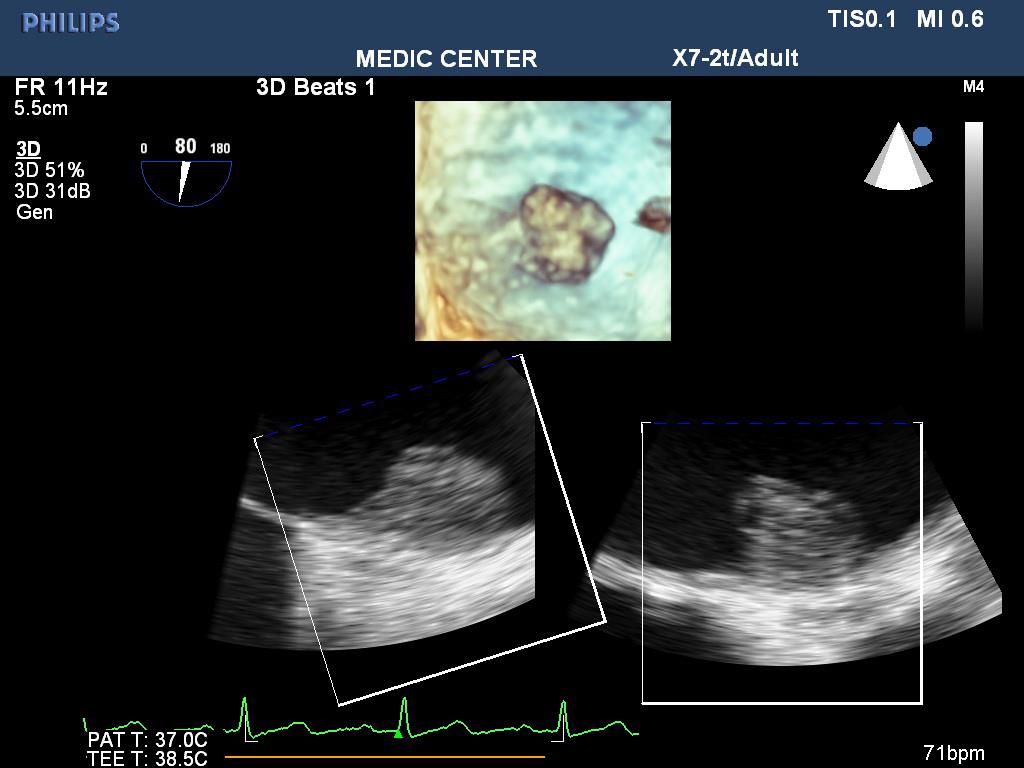

Figure 2. LA thrombus on 3 D TEE; “TEE image from Nguyen Tuan Vu”

TTE identifies the disease. TEE detects spontaneous contrast and thrombi in LA, LAA of patients with mitral stenosis. It is important to decide using anticoagulation before percutaneous balloon mitral valvuloplasty or surgery (Figures 1-8).

TTE can detect LA thrombus but the sensitivity is low. TEE is the credible technique to detect LA and LAA thrombi, with values of sensitivity and specificity about 99% [13].